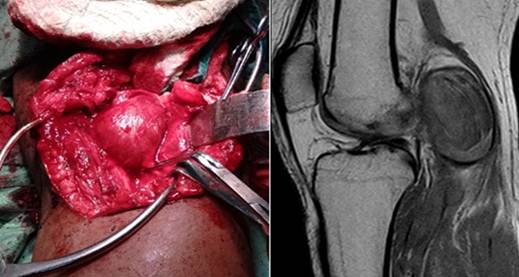

El diagnóstico diferencial del QB se realiza con otras tumoraciones de la fosa poplítea, dentro de las que se encuentra el aneurisma de arteria poplítea (AAP), esta enfermedad es el principal aneurisma periférico y el segundo en frecuencia después del aneurisma de la aorta (Fig.2).

Según Leake AE et al. 29 se define como aneurisma una dilatación mayor al 50 % del diámetro del vaso sanguíneo, en caso de la arteria poplítea mayor de 1,5 cm3. Existen diferencias entre el QB y el AAP (tabla 2). 30,31